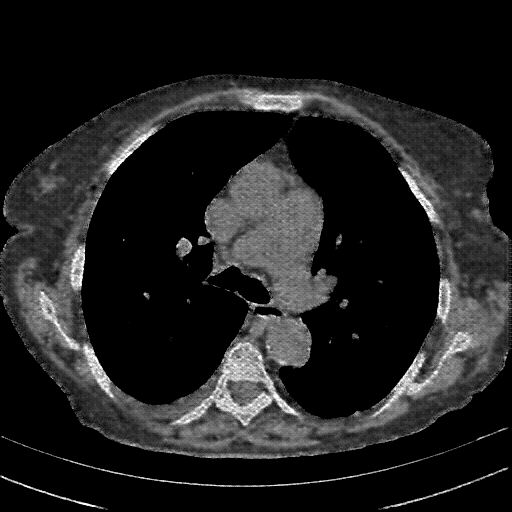

4Γ—3 grid: Rows show different image types (Original NATIVE, Reconstructed NATIVE, Original VENOUS, Generated VENOUS), Columns show windowing techniques (No Window, Lung Window, Mediastinum Window)

Original NATIVE CT scan (input)

Full window (WL 1023.5, WW 4095 β†’ Low βˆ’1024, High +3071)

Original VENOUS CT scan